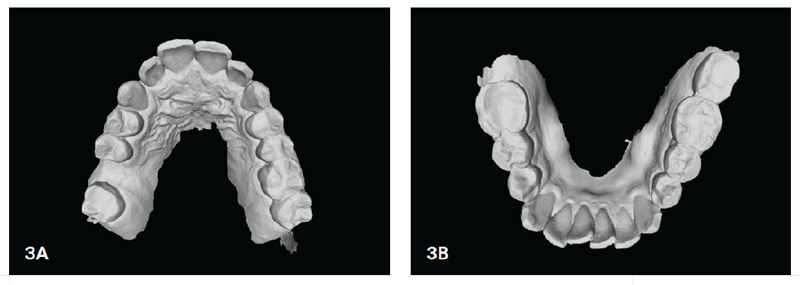

Fig. 3: Initial maxillary (left) and mandibular views.

We had a 45-year-old male patient approach us with the desire to improve his alignment, close a few small spaces (between UR2 and UR3) and prepare for dental implants in the UR6 and LR7 areas (Fig. 1). The patient’s chief complaints were crowding and minor spacing. He also had a Class I malocclusion with moderate lower crowding and mild upper crowding (U&L, 3x3), along with a need for improved arch development and coordination (Figs. 2 and 3).